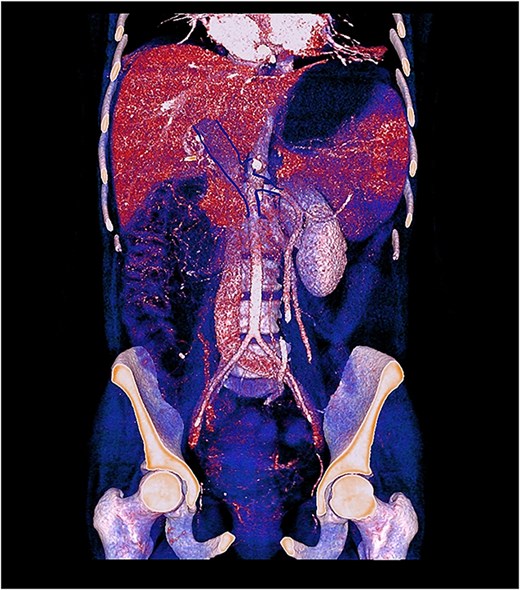

Contrast-enhanced computed tomography (CT) demonstrated thrombosis of the portal vein, splenic vein, and superior mesenteric vein with proximal dilatation, diffuse jejunal thickening, mesenteric fat stranding, and mild splenomegaly (Figs 1 and 2). No pneumatosis or portal venous gas was seen.

3D contrast-enhanced CT rendering reconstruction in venous phase showing thrombosis of the portal, splenic, and superior mesenteric veins with proximal dilatation and thickening of the jejunal wall.